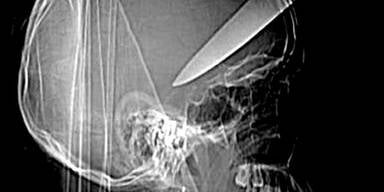

Es ist ein Wunder: Ein 16-jähriger Brite überlebte einen brutalen Angriff - ihm wurde ein Küchenmesser in den Kopf gerammt.

Einem 16-jährigen Teenager wurde ein fast 13 cm langes Küchenmesser in den Schädel gerammt, als er an einer Londoner Bushaltestelle einen Raubüberfall auf einen Bekannten verhindern wollte. Der junge Mann schritt zusammen mit zwei Kameraden beherzt ein - und wurde von den Dieben mit dem Messer attackiert. Ihm rammten sie das Messer in den Schädel, der zweite Bekannte erlitt eine Rückenverletzung, der Dritte wurde an der Schulter getroffen.

Der junge Mann überlebte die schwere Kopfverletzung nur, weil er sofort in ein Spital eingeliefert und einer Notoperation unterzogen wurde. Zehn Monate wurde er entlassen, und besuchte wieder die Schule.